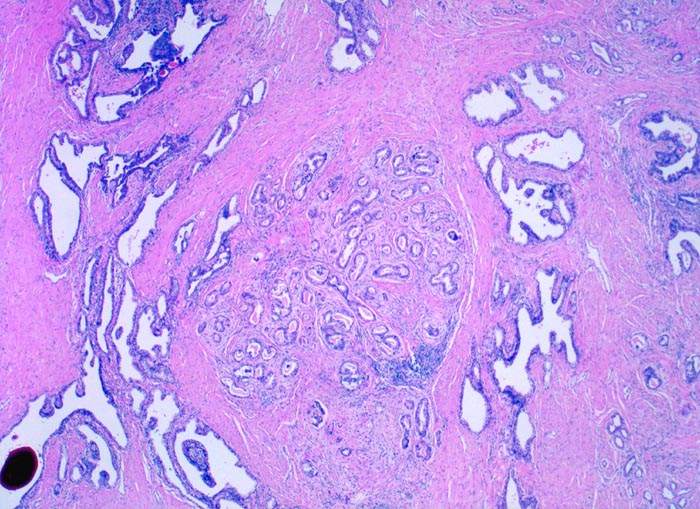

Neben grossen normalen Prostatadrüsen mit grossen Lumina ist in der Übersicht ein gut umschriebener Herd dicht gelagerter mittelgrosser gut geformter Drüsen mit intraluminalem Sekret erkennbar. Innerhalb dieses Karzinomherdes sind keine normalen Drüsen erkennbar. Das Karzinom infiltriert also nicht das Normalgewebe. Dieser Tumorherd entspricht einem Gleason Grad 2.

Eingedicktes Sekret mit Ausbildung eines Corpus amylaceum in einer benignen Drüse.

Die Diagnose eines Prostatakarzinoms lässt sich bereits in der Übersichtsvergrösserung aufgrund der Ansammlung kleiner Drüsen stellen. Ein umschriebenes noduläres Infiltrat grösserer gut geformter Karzinomdrüsen, welches das normale Prostatagewebe intakt lässt, entspricht einem Gleason Grad 2.